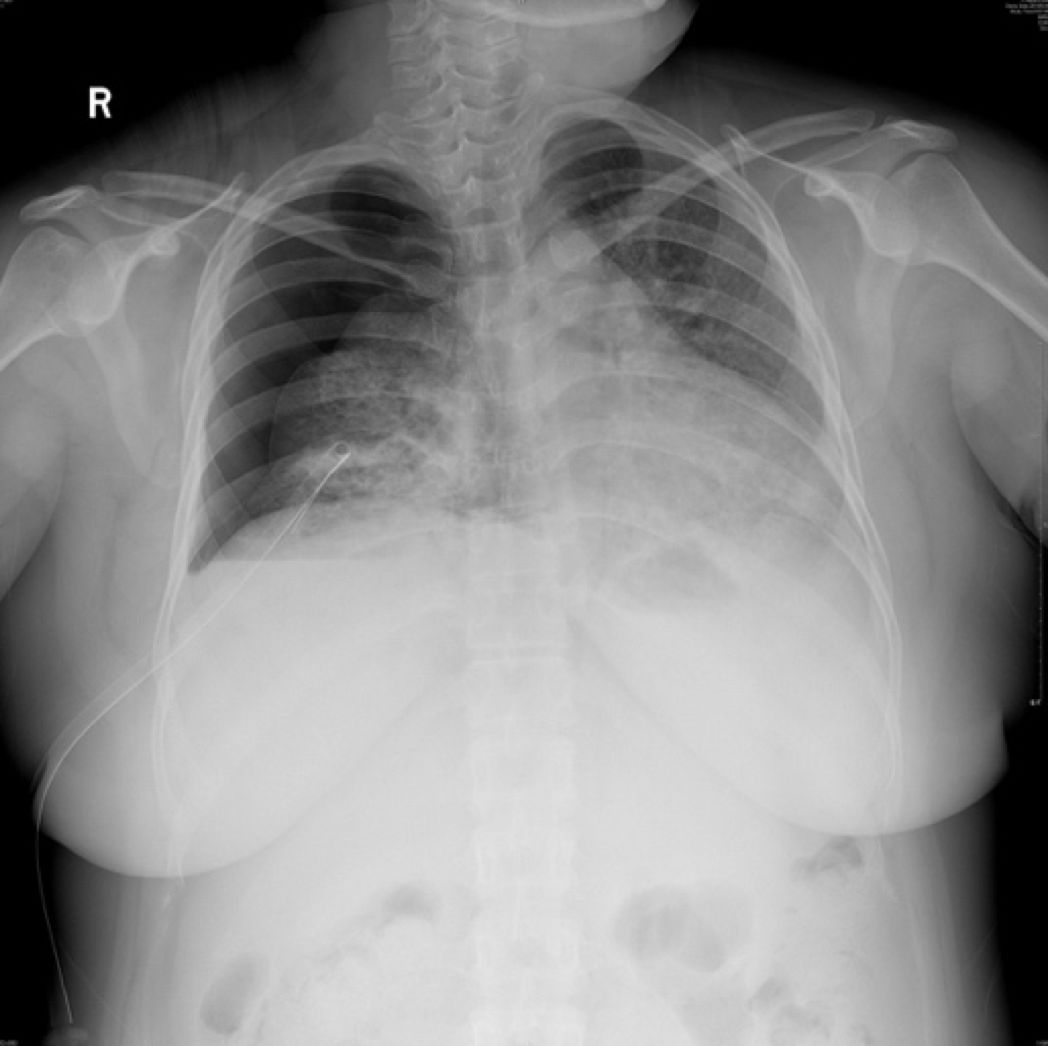

2019-5-14我院胸部CT平扫

患者青年女性,因「咳嗽、咳痰、咯血半月余,胸痛8天」入院,急性起病,逐渐加重,胸部CT提示右侧气胸,双肺相对弥漫分布的气囊与结节,沿气管血管束分布,右下肺实变。肺部弥漫性囊泡样疾病,需要考虑肺淋巴管平滑肌瘤病(LAM)、BHD综合征、肺朗格汉斯组织细胞增生症(PLCH)、淋巴细胞性间质性肺炎(LIP)、感染性疾病如耶氏肺孢子菌肺炎(PCP)等疾病。LAM一般常见于育龄期女性,影像学以弥漫均匀分布的薄壁囊泡为主要表现,此例患者为年轻女性,肺部多发囊泡,需要考虑LAM,但囊泡不是薄壁,分布不均匀,形状不规则,不符合LAM的典型表现。PLCH一般多见于吸烟患者,影像学以奇形怪状的沿支气管血管束分布的囊泡样改变为特点,吸烟患者一般以上叶及中叶病变为主,不累及肋膈角,多系统病变患者可以累及肋膈角,本例需考虑PLCH可能。BHD综合征肺部表现为多发薄壁囊肿,形状不规则,多于基底部、外周、沿纵隔分布,其他系统表现可合并皮疹、肾肿瘤等,可有家族史,本例患者无BHD家族史,需进一步排查其他器官有无病变。LIP常有肺部多发囊泡改变,一般合并自身免疫性疾病,该患者需进一步完善自身抗体等风湿免疫相关指标,协助诊断。此外,还需考虑PCP、金葡菌感染等感染性疾病。PCP多见于免疫抑制宿主,可以有多发性肺气囊的表现,该患者无发热,无免疫抑制病史,目*考前**虑可能性不大。

本例患者的胸部CT主要表现为两肺相对弥漫分布的怪异的气囊和结节,气囊为薄壁,以中上肺分布为主,沿支气管血管束分布,符合LCH细胞沿支气管分布的特点,并且有可能会引起支气管阻塞,类似活瓣样的作用,因此囊腔的形状怪异。胸腔镜术后的CT表现,可能是局部阻塞牵拉引起疱的加重,也可能是胸膜粘连后局限性的气胸的表现。